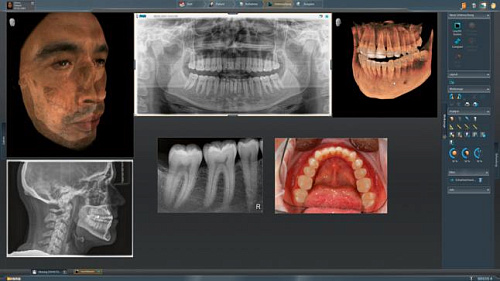

Модернизированный сенсорный экран Easypad с понятным и удобным интерфейсом позволяет выставить наилучшие параметры контрастности и разрешения. Систематизация данных по диагностике становится значительно удобнее и проще с ПО обработки изображений SIDEXIS 4, ORTHOPHOS.

1. Двух-и трёхмерные снимки совмещаются в одной программе

2. В одном окне можно сравнивать разные 3D-результаты

3. Считанные минуты уходят на просмотр анамнеза пациента.